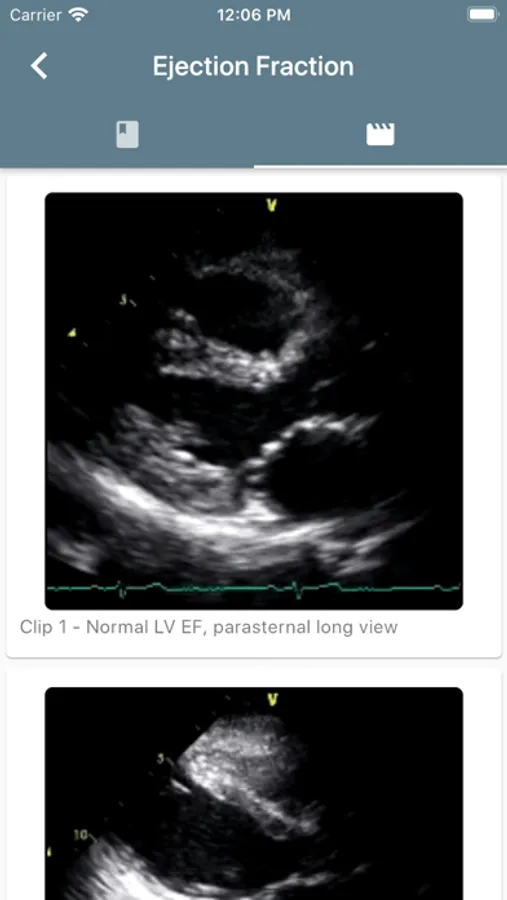

Practice ultrasound and take measurements while using the app to optimize images and measurements. The educational content will allow successful and accurate qualitative and quantitative assessments.